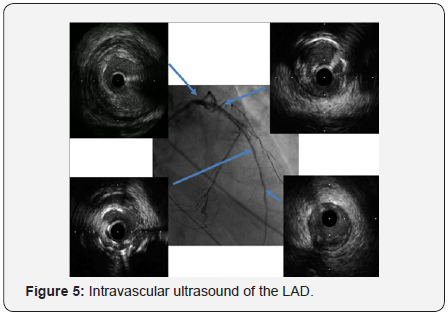

In order to perform (PCI) left trans-radial (TR) access was established then with the use of sheath-less technique seven French system (7F EBU4) (Launcher Medtronic) guiding catheter (GC) was used to engage the left main coronary artery (LMCA). A 0.014 Fielder FC guidewire (GW) was loaded on single lumen micro-catheter (MC) and was used to re-canalize CTO from mid LAD. After failure to do so using two Fielder FC guidewires, we switched to a Fielder XT-A guidewire which was successful to pass to the severely calcified mid to distal LAD with ante-grade approach. With anchoring balloon technique a 2.0x20mm Mini-Trek balloon at D2 branch at 12 atmospheric pressure unites (atm), we inflated a 1.2x6mm Mini-Trek(Abbott Vascular) balloon at 16-20atm at the CTO cap, then 2.0x20 Mini- Trek balloon at mid to distal LAD at 18-20 atm. Long dissection from very distal LAD was noted. To facilitate delivery of stents a 0.009” Rota Wire was substituted for Fielder FC to very distal LAD and rotational atherectomy (RA) de-bulking was done in a stepwise manner with 1.25 mm, then 1.5 mm burr at 180K-220K rpm as illustrated in Figures 3 & 4. We dilated the whole LAD with 2.0x20mm Mini-Trek at 20 atm then 2.5x15mm Hiryu (TERUMO) high pressure balloon (HBP) at 28 atm at proximal to mid LAD, then 3.0x15mm Hiryu HPB was inflated at p-m- LAD at 24-26 atm in order to facilitate stent passage through calcified mid LAD, subsequently we interrogated the LAD with intravascular ultrasound (IVUS) as illustrated at Figure 5.